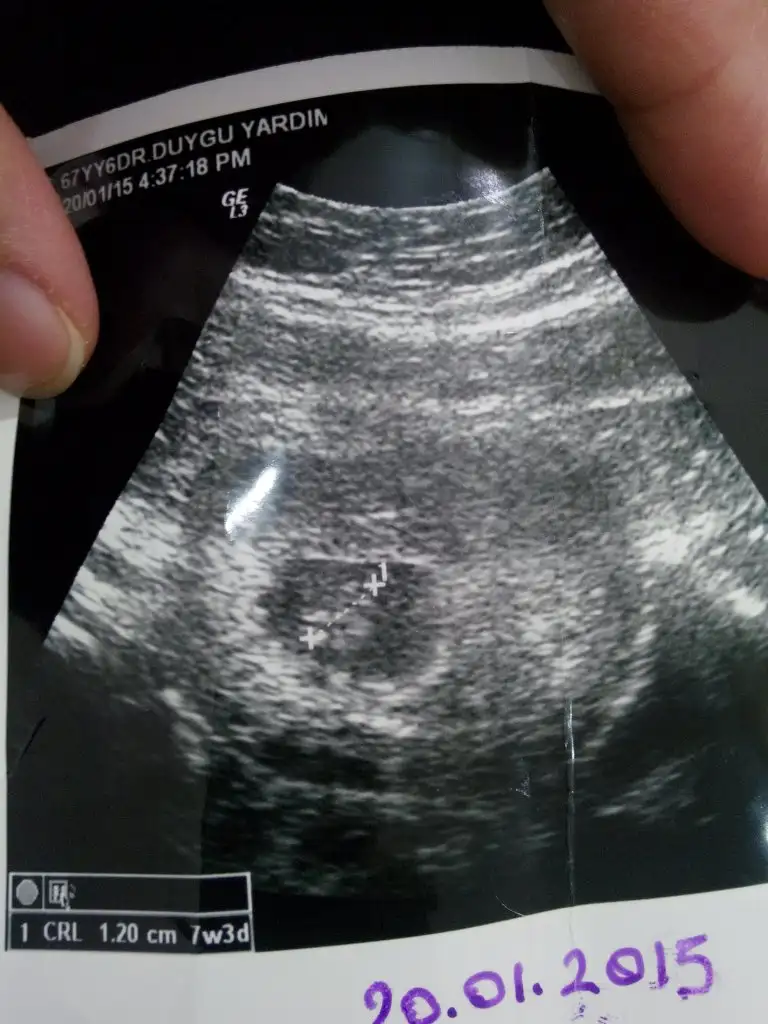

Eki Görüntüle 1439859

Bende tam 7 8 yada 9 haftalarda foto varmi diycekyim :))Cnm seni yordm amaaa.ozamn son olarak bi yorm istyrm 7+2 burdaaa.cokkk tesekkrlrrr

Keseye gore erkek kesenin solunda :))Cnm seni yordm amaaa.ozamn son olarak bi yorm istyrm 7+2 burdaaa.cokkk tesekkrlrrr